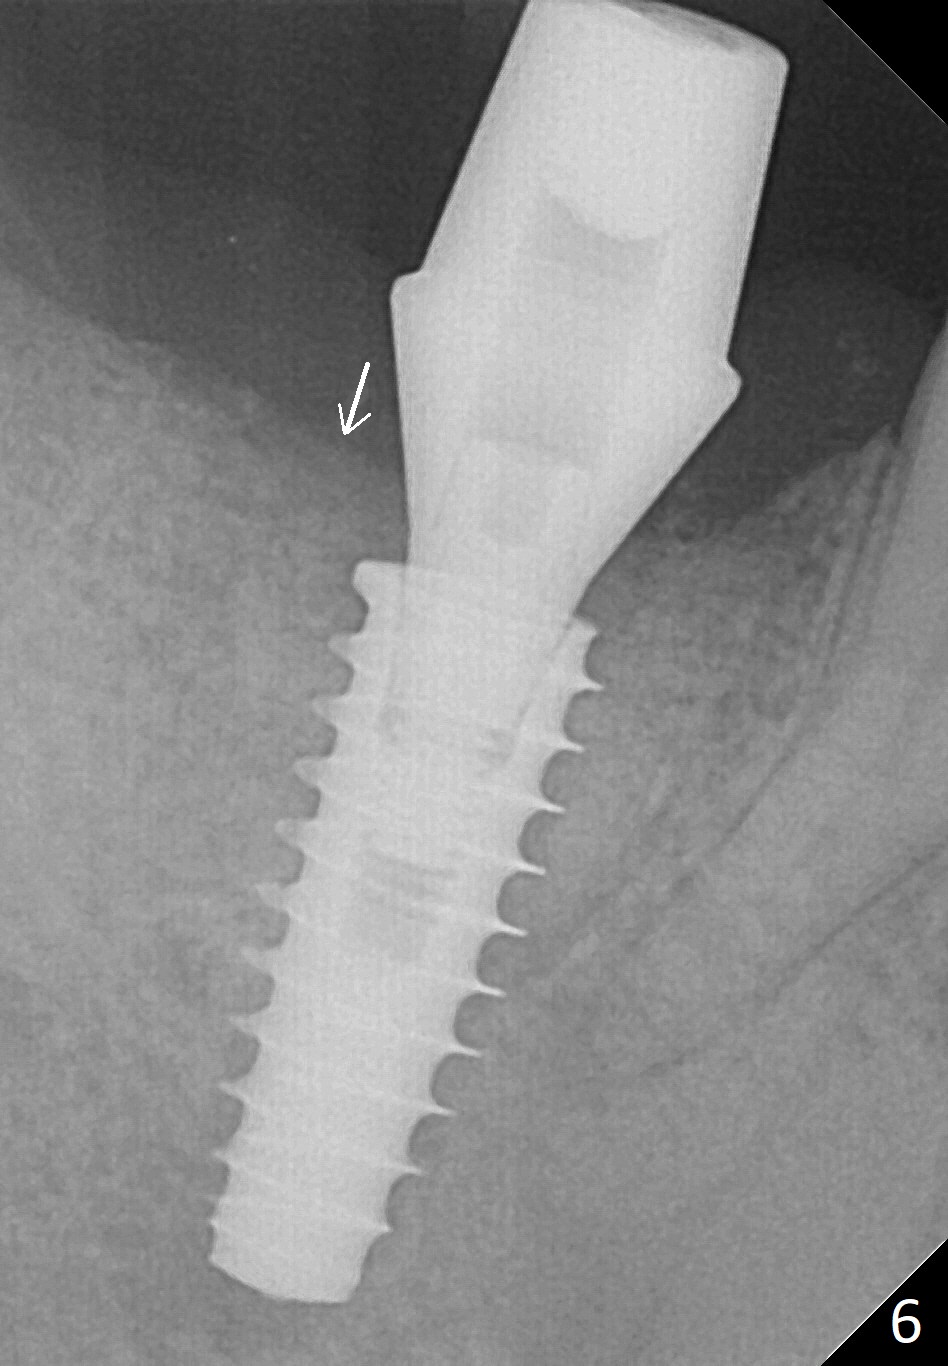

Bone graft seems to sink down and becomes denser 3 months postop (Fig.6 arrow). The bone continues being denser 5 months postop (Fig.7). There is periapical radiolucency of the tooth #29 (^). RCT is done (Fig.8). The pain persists 2 weeks postop (Fig.9,10). There is no missing canal (Fig.9). The apex is close to the implant (Fig.9 *). Apicoectomy will be performed if needed. It appears that the implant is also placed buccal (Fig.10 <) and/or the implant too large for the site. Therefore there should be a 2-3 mm buccal gap before and after implant placement. Separation and reflection of the buccal flap allows better visibility. The pain persists 1 month post RCT and 6 months post implant placement. RCT retreatment is initiated (Fig.11,12) with placement of Calcium Hydroxide paste after redebridement with 30/.04 rotary file at 23.5 mm (.5 mm longer than the earlier RCT, Fig.13). RCT retreatment finishes with apparent transportation and extrusion in 4 weeks (Fig.14,15), followed by apicoetomy (Fig.16,17) (20 days later)). Discomfort remains 2.5 months postop (Fig.18). Keep watching.